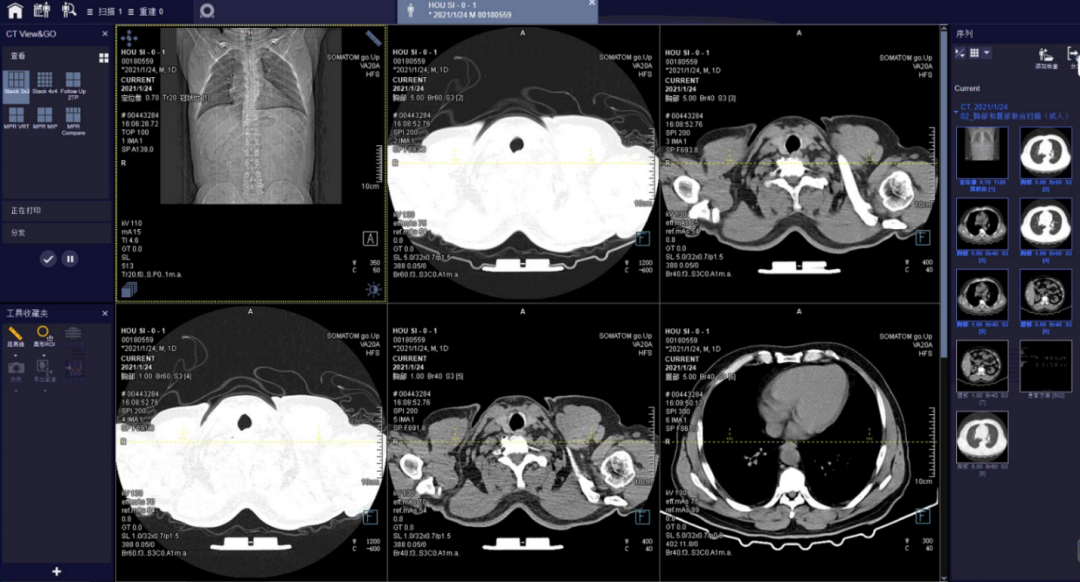

•  CT View&go中,进行图像浏览、三维、打印及分发等操作。

方舱ct怎么取西门子医疗方舱CT操作指南_https://www.jmylbn.com_新闻资讯_第15张